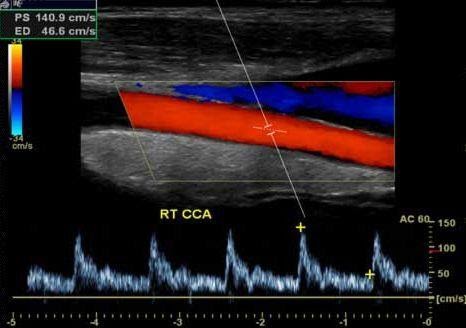

Режимы УЗИ на основе эффекта Допплера

PW - импульсно-волновой допплер. Данный режим позволяют оценить отдельные зоны по глубине. Используется для обеспечения анализа потока в конкретных объектах внутри исследуемого сосуда.

Flow - цветной допплер - ЦДК. Учитывает приближающийся и удаляющийся кровоток, применяется для исследования кровотока в сосудах, в эхокардиографии. В сочетании с энергетическим допплером помогает в дифференциации кист и опухолей.

Дуплексные и триплексные режимы (B+Color+D)

Дуплексный режим позволяет выявлять патологии каналов, нарушение их функций.

На его основе можно сделать вывод о строении вен и артерий, степени их сужения, выявлять патологии в строении сосудистой системы, поставить точный диагноз.

Триплексный режим расширяет возможности дуплексного. Добавляет режимы цветного допплера, по которым можно наглядно судить о направлении кровотока и его скорости, Также позволяет более точно оценить проходимость сосудов и степень стеноза.